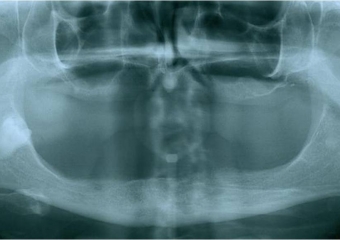

Raio x inicial